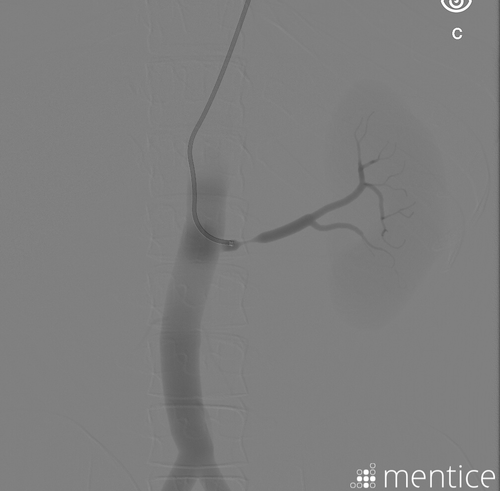

Mentice Renal Intervention is designed for the training of renal angiography, angioplasty, stenting, and management of renal bleeding caused by perforation. Various lesion locations, anatomical variations, and other learning challenges are presented. Practice with this module will improve the learner’s understanding of therapeutic treatment options in patients with hemodynamically significant renal artery disease. The entire training procedure is performed in a learner-focused, risk-free environment using real clinical devices.

Renal revascularization is mainly requested to investigate renal artery stenosis, flush pulmonary edema, and rapidly decreasing renal function. Renal artery angioplasty and stenting is a complex procedure—this module focuses on teaching fundamental techniques to junior fellows. Experience in all aspects of peripheral angioplasty and familiarity with interventional devices and associated techniques is important. This module features a variety of renal lesions, anatomies, the possibility to practice alternative access, such as radial or femoral approach, for severly angulated renal takeoffs, as well management of complications, such spasms and renal bleedings.